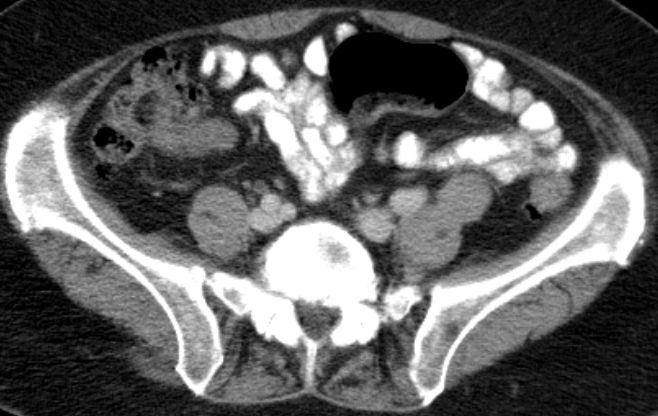

| Metastasierung | vergrößerten Lymphknoten lateral der A. iliaca externa links